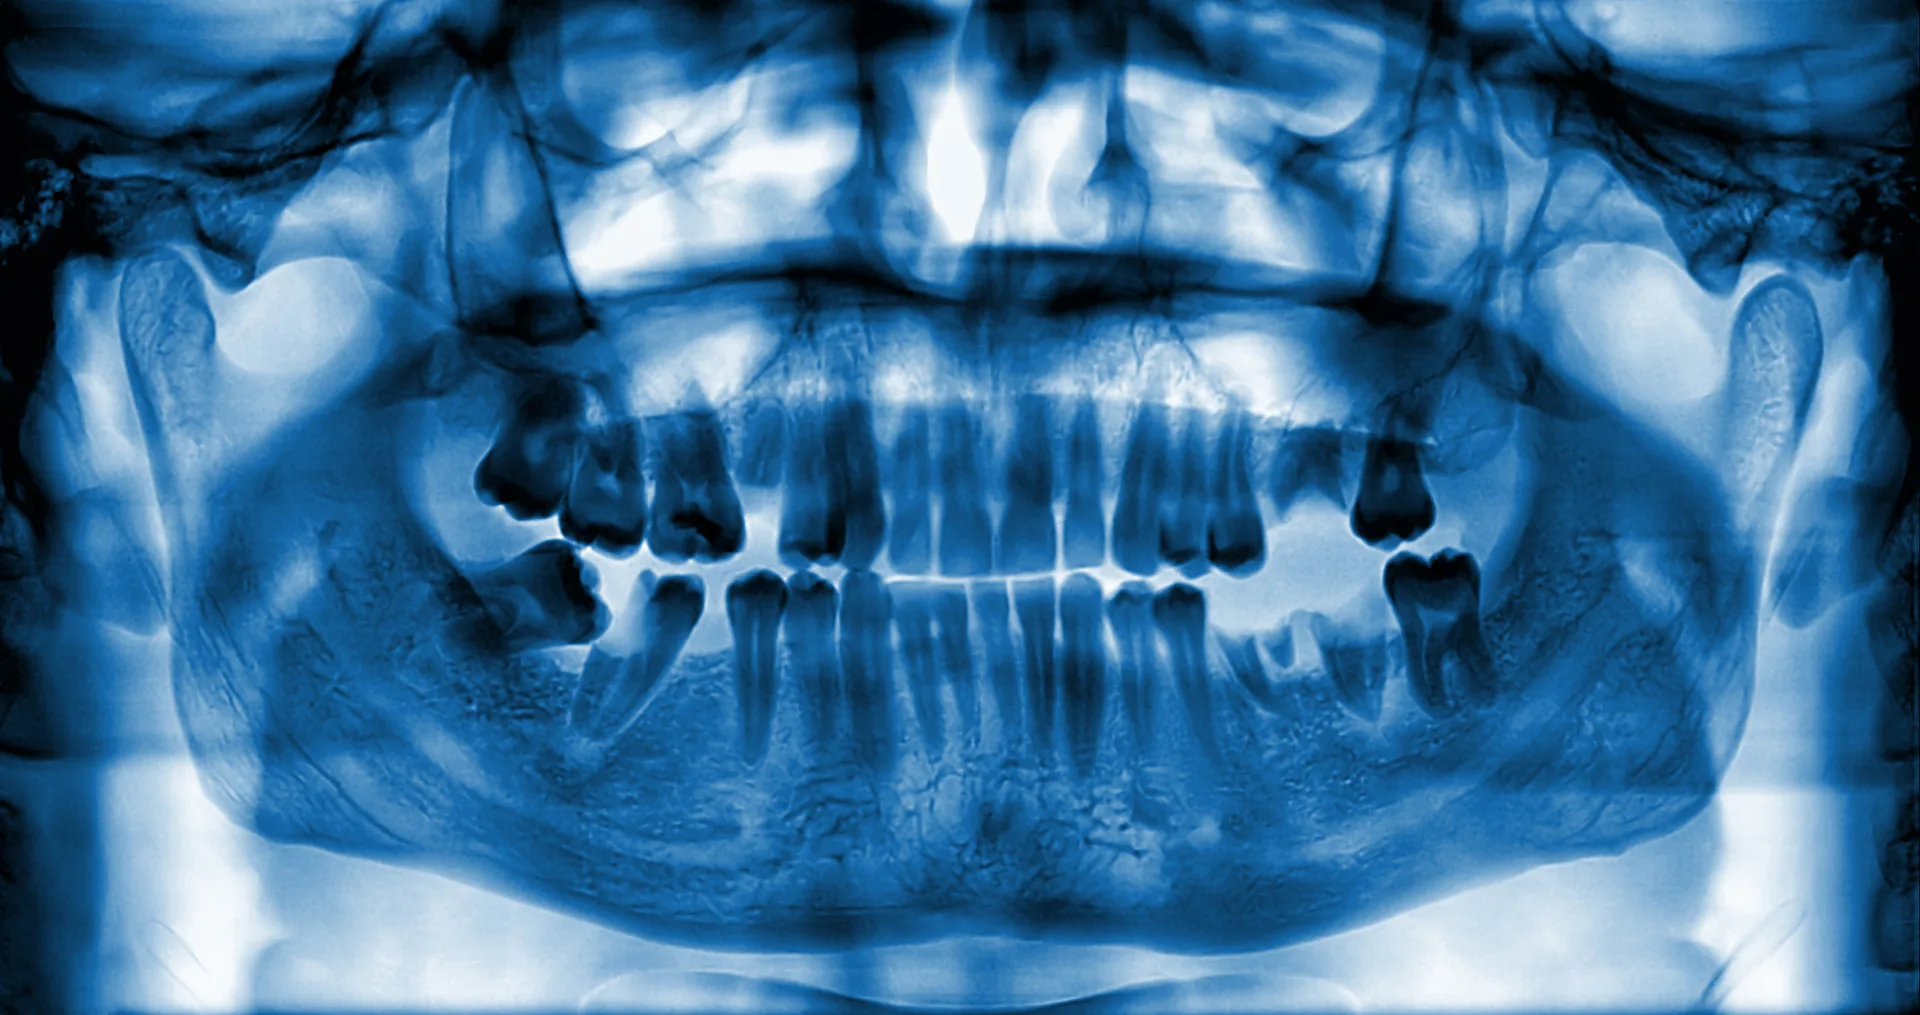

If you’ve struggled from jaw bone loss due to missing teeth, you’re not alone, and there’s a solution to get you smiling again. A ridge augmentation recreates the natural contour of the gums and jaw bone, restoring its form and creating a solid foundation for implants.

After tooth extraction, the jaw bone may need to be rebuilt and reshaped to make sure that your mouth can accommodate a dental implant, or for aesthetic purposes. Not everyone needs ridge augmentation, but it’s often done immediately after tooth extraction to avoid the need for another surgery. If your oral surgeon believes that your jaw bone may need strengthening, it’s a good idea to get ridge augmentation during your tooth extraction procedure.